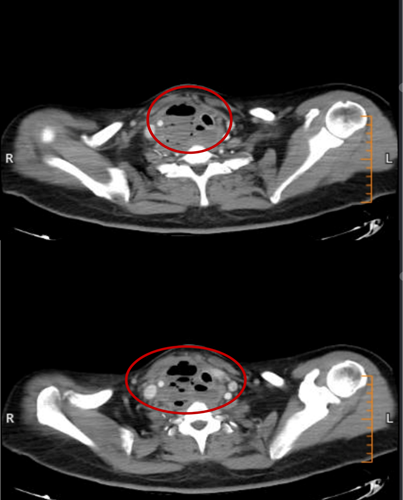

2月15日与20日,当整座城市沉浸在辞旧迎新的欢声笑语中,两位病情凶险的颈部深部脓肿患者先后被推入耳鼻咽喉头颈外科。他们都有多年糖尿病病史,春节期间饮食不规律、作息紊乱、血糖波动大,让原本隐匿的感染如野火般迅速蔓延。其中一位患者的感染已突破颈部间隙,如藤蔓般向下侵入纵隔区域——那里是心脏、大血管、气管的“交通枢纽”,是人体最脆弱的生命禁区之一。CT影像上,脓肿中密布的气腔像一个个危险的信号,气管被严重受压,每一次呼吸都变得艰难。文献数据冰冷而沉重:颈深部脓肿并发下行性纵隔炎,病死率高达40%~70%。时间,从未如此紧迫。

患者乙CT示:颈部咽后间隙—右侧咽旁间隙—右侧颈动脉间隙脓肿